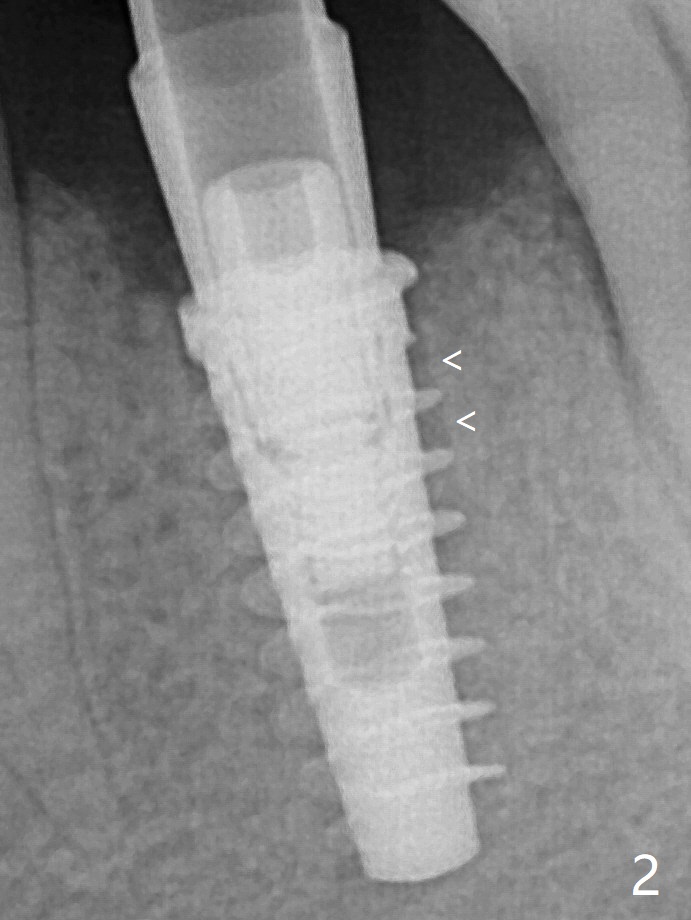

放置基台前,骨粉放置低于植体上端(Plateau),但是远中仍有间隙(图二箭头)。 放置基台后,两度填骨粉(图三*),远中间隙仿佛消失(箭头)。术后两个月,植体顶端似乎被牙槽嵴覆盖了(图五)。